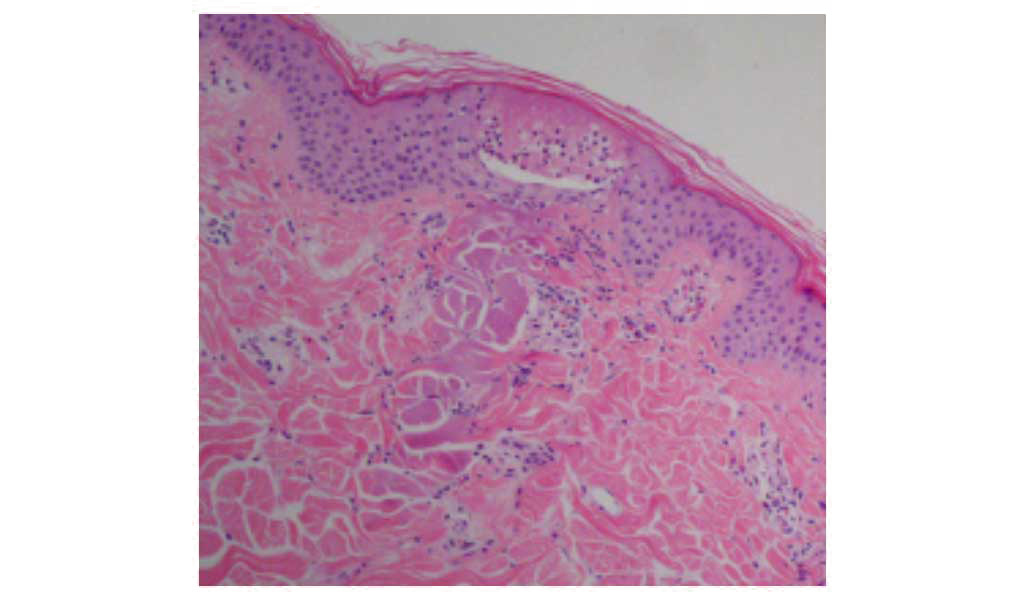

従来のレーザー治療がターゲット全面へ照射するのに対し、フラクショナルレーザーは点状にレーザービームを照射を行います。

レーザーによる周辺組織へのダメージが少ない

フラクショナルレーザーは、CO2フラクショナルレーザーに比べ、凝固層がほとんどない治療(蒸散)が可能です。